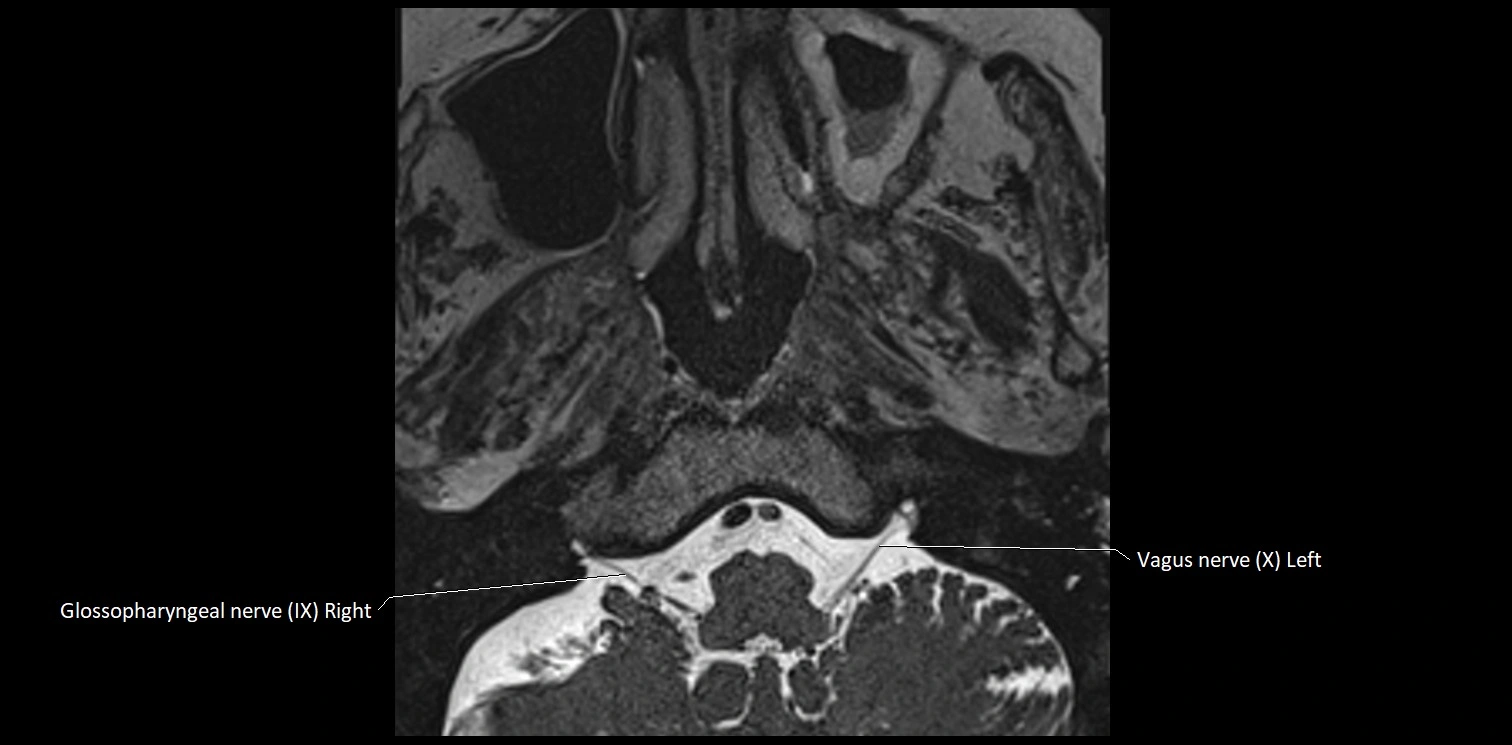

MRI Appearance

• The abducens nerve is a small, thin, linear structure

• Best visualized on high-resolution T2-weighted 3D MRI sequences (e.g., FIESTA or CISS)

• Seen as a hypointense (dark) line running from the brainstem at the pontomedullary junction, traversing the prepontine cistern, and entering Dorello’s canal under the petrosphenoidal ligament, then into the cavernous sinus, and finally the orbit

• May be challenging to visualize in standard MRI due to its small size

• Pathology may be inferred by absence, displacement, or enhancement of the nerve